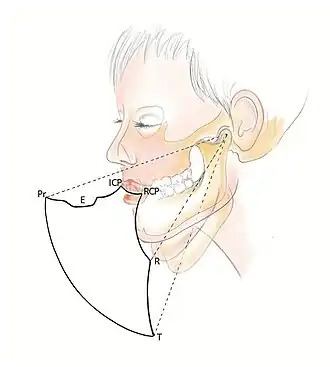

When the mandible is in this retruded position, it opens and closes on an arc of curvature around an imaginary axis drawn through the centre of the head of both condyles. This imaginary axis is termed the terminal hinge axis. The first tooth contact that occurs when the mandible closes in the terminal hinge axis position, is termed Retruded Contact Position (RCP).[13] RCP can be reproduced within 0.08mm of accuracy due to the non-elastic TMJ capsule and restriction by the capsular ligaments, thus it can be considered a ‘border movement’ in Posselt’s envelope.[14]

Centric Occlusion (CO) is a confusing term, and is often incorrectly used synonymously with RCP. Both terms are used to define a position where the condyles are in CR, however RCP describes the initial tooth contact on closure, however this may be an interference contact. On the other hand, CO refers to the occlusion where the teeth are in maximum intercuspation in CR. Posselt (1952) determined that only in 10% of natural tooth and jaw relationships does ICP = CO[14] (maximum intercuspation in CR) and so the term RCP is more appropriate when discussing the occlusion that occurs when the condyles are in their retruded position. CO is a term that is more relevant to complete denture application or where multiple fixed unit prosthodontics are provided, where the occlusion is arranged so that when the mandible is in CR, the teeth are interdigitating.

Posselt's Envelope of Border Movements

Posselt’s Envelope of Border Movement (often referred to as the 'border movements of the mandible') is a schematic diagram of the maximum jaw movement in three planes (sagittal, horizontal and frontal). This encompasses all movements away from RCP, and includes:

- Protrusive movements: When the mandible moves forward from centric relation, this is considered as protrusion.[12] In Class I occlusion, the predominant contacts occur on the incisal and labial surfaces of the mandibular incisors and the incisal edges and palatal fossa areas of the maxillary incisors.[6]

- Lateral movements: When the mandible moves to the left or right, the mandibular posterior teeth move laterally across the opposing teeth. For example, when the mandible moves to the right, the right mandibular teeth move laterally across their opponents and this is termed the working side of the mandible (the side towards which the mandible is moving). In contrast, the left mandibular teeth move medially, downwards and anteriorly across their opposing posteriors and this is called the non-working side (the side to which the mandible is moving away from).

- Retrusive movements: This is when the mandible moves posteriorly from ICP. Compared with protrusive and lateral movements, retrusive movements are generally considerably smaller with a range of movement around 1 or 2 mm due to restriction by the ligamentous structures.[2]